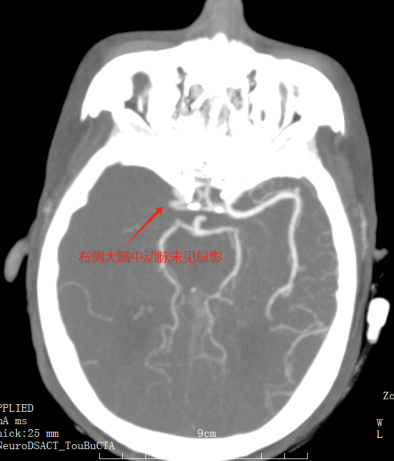

卒中中心值班医师(绿道医师)马上给予指示:收费处绿色通道挂号,院前医师车上完成血液抽取、血糖及心电图检查,并将患者绕行急诊紧急送往CT室进行头颅CT检查。患者心电图显示I、AVL、V5、V6导联ST段明显改变,考虑同时合并急性冠脉综合征,患者存在急性心梗的可能。随即加查肌钙蛋白,同时送检头颅CT平扫+CTA检查。CT检查结果明确了患者右侧大脑中动脉的M1段闭塞,确诊为急性脑梗死。肌钙蛋白检测结果亦回报:12.83ug/ml,结合心电图的表现,确诊为急性非ST段抬高型心肌梗死。

头颈CTA示右侧大脑中动脉起始处闭塞